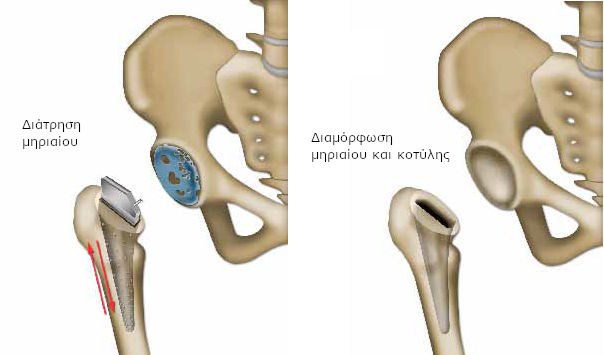

Ο χειρουργός «κόβει», βάσει προηγούμενων υπολογισμών, το ανώτερο τμήμα του μηριαίου (κεφαλή μηριαίου), που παρουσιάζει φθορά του χόνδρου και το αφαιρεί.

Με ειδικές ράσπες δημιουργεί, στη συνέχεια, στο εσωτερικό του μηριαίου ένα τούνελ, για να τοποθετήσει το πρώτο τμήμα της πρόθεσης. Εάν η κοιλότητα στη λεκάνη (κοτύλη) παρουσιάζει σοβαρές βλάβες εξαιτίας της αρθρίτιδας, ο χειρουργός προετοιμάζει επίσης το οστό, αφαιρώντας το χόνδρο με ειδικές ράσπες διαφόρων μεγεθών.